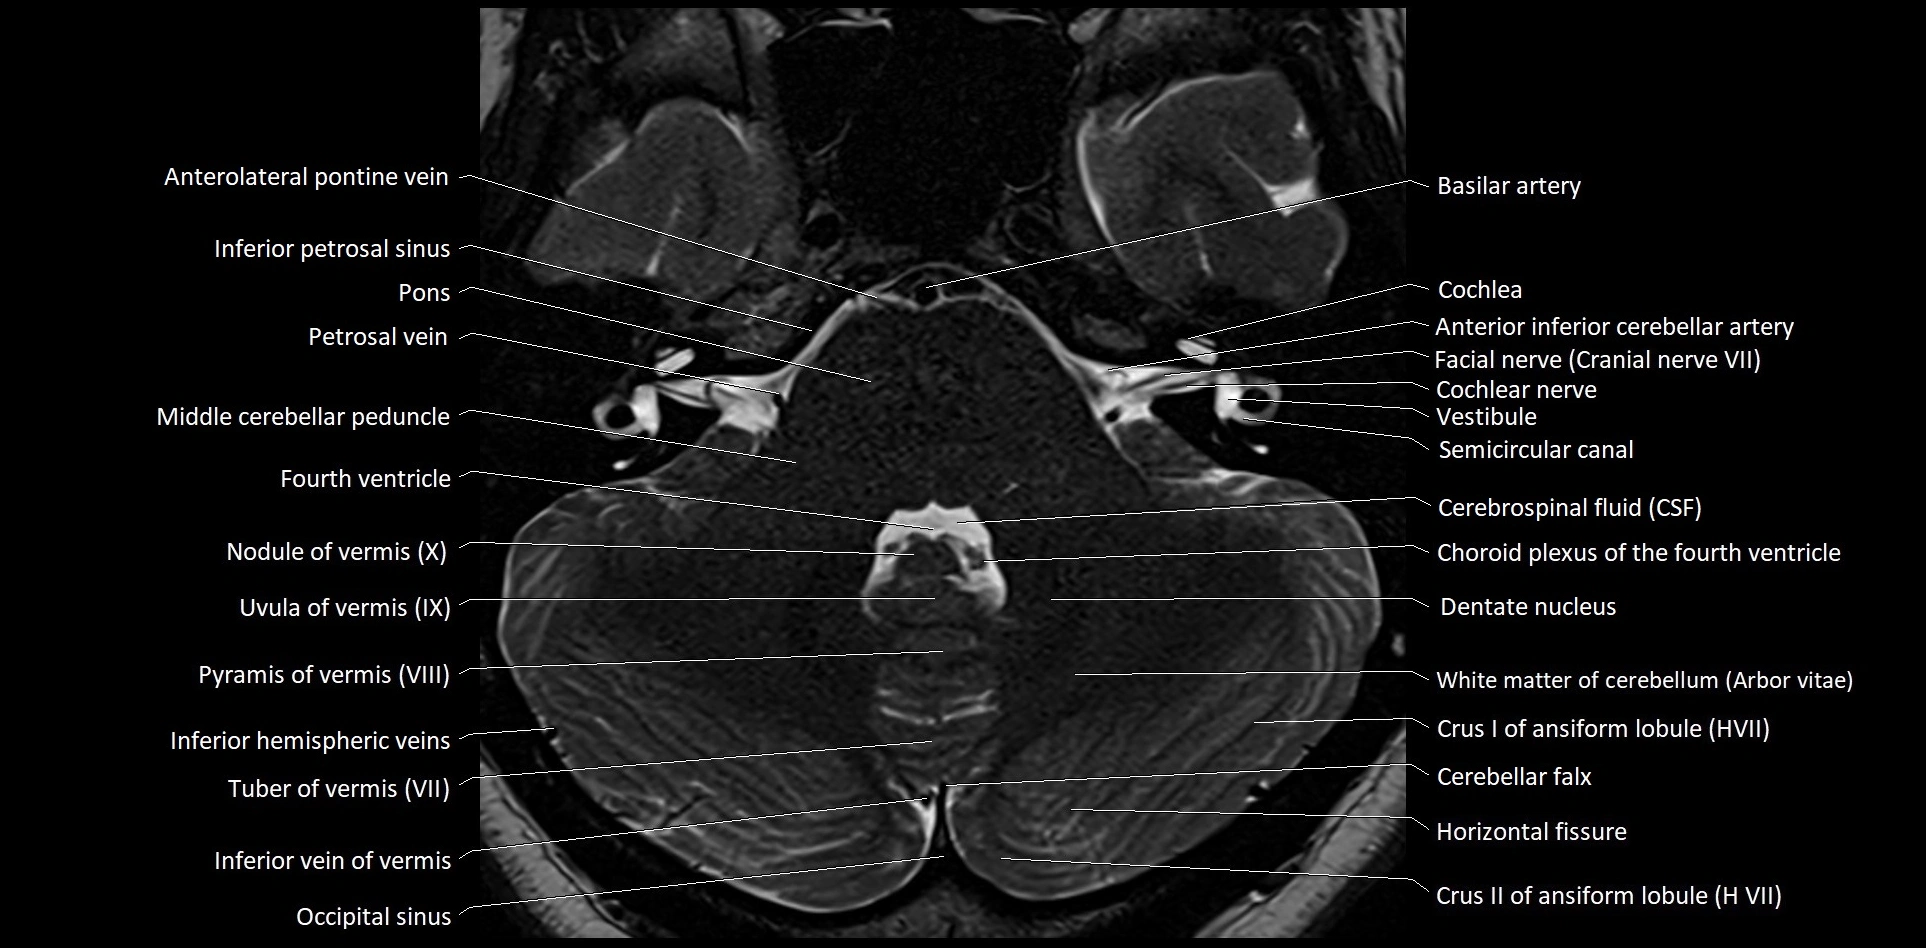

MRI images